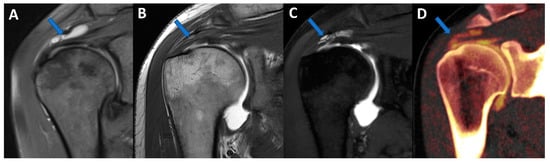

Figure 1.

Recurrent anterior shoulder dislocation in a previously operated patient. By using multiple applications, DECTA can help in the diagnosis of anterior shoulder dislocation, potentially representing a “one-stop one-shop” procedure. A blended virtual 120 kVp axial CTA image (A) shows anterior labral and glenoid rim disruption (arrow). A VNC image on the axial (B) and sagittal (E) planes helps in the evaluation of bone morphology, allowing correct glenoid surface measurement (arrow). In the axial iodine map (C), it is possible to better evaluate the morphology of the anterior labrum (arrow). In the axial BME 2D superimposed image (D), it is possible to recognize edema of the anterior glenoid rim (blue arrow) and subtle edema of the posterior aspect of the humeral head (white arrow), which is consistent with recent recurrent dislocation.

Figure 4.

Complete supraspinatus tendon diagnosed using DECTA. On the coronal standard STIR MRI image (A), a fluid collection located on the bursal side of the supraspinatus tendon can be identified (arrow). On the coronal T1 weighted TSE MRA image (B), the supraspinatus tendon appears irregularly thinned, as in a case of a partial tear. There is no apparent passage of contrast material on the bursal side (arrow). On the corresponding 1 mm PD fat-saturated image of the coronal plane (C), there are still no clear signs of complete tendon tears (arrow). The reconstructed DECTA 1 mm coronal image (iodine map; (D)) clearly demonstrates the presence of a complete tear with the passage of contrast material on the bursal side of the tendon (arrow).